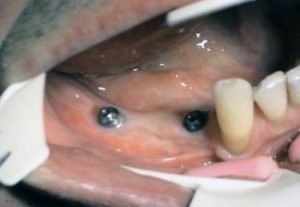

2. PHASE - state before the provisional solution was made

Prosthetic treatment in a toothless jawbone carried - 4 implants